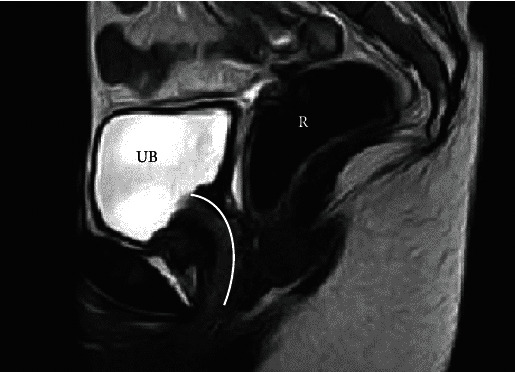

简介Mayer-Rokitansky-Küster-Hauser(MRKH)综合征是一种女性先天性疾病,其特征是阴道和子宫发育不全或缺失。创造新阴道的一线治疗方法是由患者自己进行阴道扩张术。我们在此报告了一例罕见的 MRKH 患者,该患者出现尿道扩张,并成功接受了 Davydov 阴道成形术。病例报告:17岁的患者已知为单肾,妇科医生对其进行了会诊,并确诊为MRKH综合征。由于患者的尿道扩张是由于反复的尿道内性交造成的,因此无法通过自行进行阴道扩张术来形成阴道。然而,Davydov阴道成形术却成功地完成了,术后没有出现任何并发症,患者术后完全恢复了性生活。结论MRKH 患者和医疗服务提供者应该了解尿道内性交的损害性后果。需要报告更多的病例,以确定正常性生活的最佳治疗方案。

Introduction: Mayer-Rokitansky-Küster-Hauser (MRKH) syndrome is a female congenital disorder characterized by an underdeveloped or absent vagina and uterus. The first-line treatment to create a neovagina is patient-performed vaginal dilatation. We report here the rare case of an MRKH patient who presented with urethral dilatation and was successfully treated with Davydov vaginoplasty. Case Report: Seventeen-year-old patient with known single kidney was consulted by a gynaecologist, and a diagnosis of MRKH syndrome was established. As the patient had urethral dilatation-resulting from repetitive intraurethral intercourse-neovaginal creation by means of self-performed vaginal dilatation was precluded. Rather, the Davydov vaginoplasty was successfully performed; there were no postoperative complications, and the patient was fully continent postsurgery. Conclusion: MRKH patients and healthcare providers should be educated on the damaging consequences of intraurethral intercourse. More cases need to be reported to establish the best treatment options for a normal sexual life.